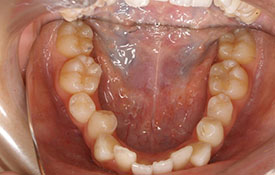

インビザラインの治療例:CASE-2

| プロフィール | 15歳 男性 |

| 所見 | アメリカから転院されて来られた方です。 インビザラインで上下顎の矯正治療を開始し下顎はアメリカで終了しており、上顎のみ治療の後期を担当しました。 アイライナーの装着は、1日平均22時間ほどでした。 |